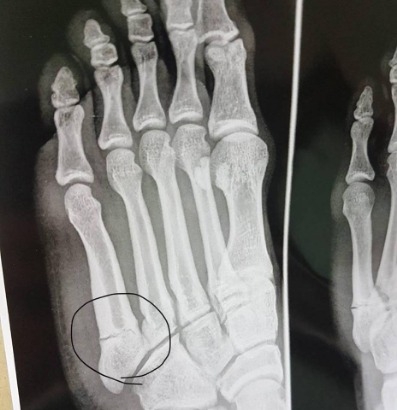

ภาพเอ็กซ์เรย์ที่เท้าของเจ้าเต๋า

ธนาสิทธิ์ ยังกล่าวถึงอาการบาดเจ็บ ที่จะทำให้หมดสิทธิ์ช่วยทีมในช่วง 2 นัดสุดท้ายว่า “เสียใจมากครับ ผมเป็นคนที่เกลียดอาการบาดเจ็บที่สุด อย่างช่วงนี้ ฟอร์มกำลังดีด้วย ก็อยากลงสนามช่วยทีมมากๆครับ แต่ในเมื่อมันเป็นแบบนี้แล้ว ผมก็คงทำอะไรไม่ได้ ก็ต้องดูแลรักษาตัวเอง เพื่อกลับมาให้ดีกว่าเดิมครับ”